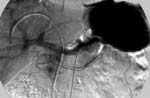

Чувствительность ангиографического исследования была несколько выше и составила 77,8% (70/90). На первом этапе работы удалось локализовать 18 из 24 опухолей (75%), а на втором 52 из 66 (78,8%). Классическая ангиографическая картина инсулиномы - гиперваскулярное образование с задержкой контрастного вещества в нем в паренхиматозную и венозную фазы (Рис. 1б,в).

Рис. 1. Продолжение.

(б, слева) Целиакография: в артериальную фазу головке поджелудочной железы определяется гиперваскулярное округлое образование размерами 12х10 мм.

(в, справа) Целиакография: в венозную фазу имеется длительная задержка контрастного вещества в образовании.